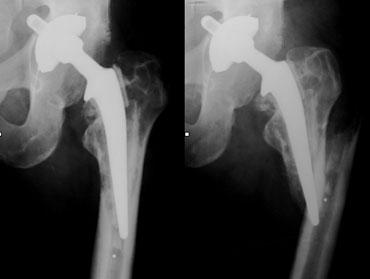

Eccentric position of femoral head within cup consistent with polyethylene wear.Focal osteolysis with endosteal scalloping in proximal femur due to particle disease.

Particle Disease

Ban đầu bệnh lý này được gọi là bệnh xi măng hoặc u hạt xâm lấn.

Đây là phản ứng mô bào xảy ra do phản ứng của đại thực bào với bất kỳ thành phần nào bong tróc khỏi bề mặt các cấu kiện của khớp nhân tạo.

Ngày nay, bệnh lý này chủ yếu gặp ở khớp háng không xi măng như một phản ứng với các hạt mài mòn polyethylene nhỏ.

Trên hình ảnh X-quang, các tổn thương u hạt xâm lấn này biểu hiện dưới dạng các vùng thấu quang khu trú xung quanh khớp nhân tạo.

Tình trạng này có xu hướng xảy ra trong khoảng từ 1 đến 5 năm sau phẫu thuật và liên quan đến hình ảnh lõm vỏ nội tủy nhẵn.

Đặc điểm then chốt là bệnh lý này không tạo ra phản ứng xương thứ phát.

Những đặc điểm này giúp phân biệt bệnh hạt nhỏ với nhiễm trùng, vốn thường có các biểu hiện xâm lấn hơn, mặc dù việc phân biệt không phải lúc nào cũng khả thi.

Mặc dù bệnh hạt là kết quả của sự mài mòn polyethylene, nhưng không phải lúc nào bạn cũng thấy các dấu hiệu rõ ràng của sự mài mòn polyethylene ở ổ cối nhân tạo.

Tuy nhiên, bất cứ khi nào thấy vị trí lệch tâm của chỏm xương đùi trong ổ cối, hãy tìm kiếm các vùng thấu quang khu trú.

Các khuyết hổng khu trú lớn có thể được phát hiện trong khi khớp nhân tạo vẫn còn vững.

Bệnh hạt tiến triển không ngừng với tình trạng lỏng khớp, gãy xương và phá hủy xương.

Đôi khi cần phải phẫu thuật thay lại một khớp háng toàn phần còn vững vì nếu mất xương nhiều hơn sẽ khiến phẫu thuật thay lại trở nên không thể thực hiện được.

Subtle eccentric position of femoral head. Even more subtle focal osteolysis around screw in acetabulum.

Bệnh do hạt mài mòn (2)

Các hạt mài mòn nhỏ từ lớp lót polyethylene được bong ra vào dịch khớp và có thể di chuyển xung quanh khớp giả thông qua các kênh nhỏ ngay cả ở những khớp háng còn vững.

Chúng có xu hướng di chuyển qua các lỗ vít (hình minh họa).

Đây là lý do tại sao các phẫu thuật viên ngày càng hạn chế sử dụng vít để cố định cốc acetabulum.

Một trường hợp khác ở bên trái.

Một lần nữa có hiện tượng tiêu xương khu trú xung quanh các vít sau khi các hạt mài mòn di chuyển qua các lỗ vít.

Vị trí lệch tâm của chỏm xương đùi trong ổ cối nhân tạo do mòn polyethylene.